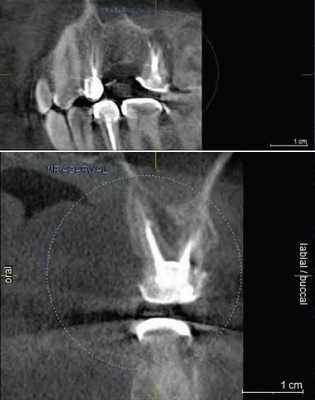

Cone beam computed tomography, complications, the inferior alveolar nerve, treatment prognosis, screening diagnostic. Одним из предсказуемых и опасных осложнений при установке дентальных имплантатов на нижней челюсти следует считать повреждение нижнего альвеолярного нерва. Работами Сирака С.В., 2006 экспериментально установлена значительная вариабельность позиции нижнечелюстного канала в теле нижней челюсти. Так, практически в половине случаев нижнечелюстной канал имеет высокое расположение, т.е. вблизи верхушек корней зубов. Столь же часто он расположен у нижнего края челюсти. Редко, когда канал занимает срединное положение. Кроме того, канал может прилежать к язычной или щечной кортикальным пластинкам, либо располагаться срединно. В ряде случаев отмечается асимметрия в положении канала с обеих сторон челюсти. В исследованиях последних лет сообщается о травме нижнего альвеолярного нерва после зубной имплантации в 13-15% наблюдений, что, безусловно, определяет практическую значимость изучения постимплантационных невритов. Изучено 24 наблюдения повреждений нерва при дентальной имплантации на нижней челюсти. Практически во всех случаях осложнение фиксировано вскоре после завершения оперативного вмешательства. Пациенты жаловались на боль различной интенсивности, потерю чувствительности нижней губы и подбородка на стороне оперативного вмешательства. Клиническое обследование, кроме стандартных методик, включало электрофизиологическую диагностику функциональных нарушений нижнего альвеолярного нерва.

Рис. 1. Асимметричное строение нижнеальвеолярного нерва, добавочный канал в области нижней челюсти справа во фронтальной проекции конусно-лучевой компьютерной томографии от Vatech.

Лучевое обследование проводилось на различных этапах имплантации. Как правило, всем пациентам выполнялась ортопантомография на дооперационном этапе. В сложных клинических ситуациях использовались дентальная объемная томография. Изучение литературных источников по топографической анатомии лицевого скелета показало отсутствие какой-либо информации о связи строения и расположения нижнечелюстного канала с вероятностью повреждения нерва при установке имплантатов. Результаты проведенных собственных рентгеноанатомических исследований челюстно-лицевой системы позволили выделить клинически значимые особенности строения и расположения нижнечелюстного канала и нерва в теле челюсти. В этой связи к предрасполагающим анатомическим факторам риска развития хирургических осложнений при дентальной имплантации могут быть отнесены:

Первая - легкая степень обусловливалась сдавлением ствола за счет отека, гематомы или прямой, непосредственной, но незначительной компрессией имплантатом. Рентгенологическое исследование посредством конусно-лучевой компьютерной томографии и программного обеспечения Ez3D-iV4.3.0 от Vatech, при маркировке нижнечелюстного канала, установило расположение дентальных имплантатов непосредственно у нижнечелюстного канала или эндопротезы перфорировали верхнюю стенку канала (Рис.2). Тактика лечения такого вида патологии основывается на сохранении имплантатов, назначении витаминов группы В, средств, оказывающих непосредственное стимулирующее влияние на проведение импульса по нервным волокнам, усиливающих сократимость гладкомышечной мускулатуры под влиянием агонистов ацетилхолиновых, адреналиновых, серотониновых, гистаминовых и окситоциновых рецепторов. Нарушение чувствительности во всех наблюдениях этой группы носило временный характер и восстановилось через 4-6 недель.

Рис.2 Конусно-лучевая компьютерная томография от Vatech. Нижнечелюстной канал маркирован с помощью программного обеспечения Ez3D-iV4.3.0.

Вторая и третья степени проявлялись частичным нарушением функции нерва, сопровождающимся различной степенью раздражения нервного ствола, болью в сочетании с парастезией или геперестезией. У этой категории обследованных чувствительность восстановилась не полностью через 1,5-2 месяца после имплантации. При проведении конусно-лучевой томографии отмечена компрессия нерва имплантатом. Измерение электропотенциалов кожи лица зафиксировало 45 мкА и выше, что свидетельствовало о нарушении проводимости нервных структур.

Результаты рентгенологического исследования показали, что дентальная объемная томография наиболее информативный метод при оценке степени повреждения нижнего альвеолярного нерва. Истинное трехмерное изображение исследуемого объекта и вращение его вокруг любой из трех осей на 360 градусов, позволяют визуализировались положение имплантата по отношению к нижнечелюстному каналу и документировать степень его повреждения. Программное обеспечение Ez3D-iV4.3.0 от Vatech предполагает огромный функциональный набор. Применительно к диагностике повреждения нерва после имплантации в данном софте в режиме высокого качества разрешения возможна трехпроекционная реконструкция, с возможностями переориентации осей, с измерением габаритов объекта исследования в масштабе 1:1(рис.3).

Рис.3 Конусно-лучевая компьютерная томография от Vatech. На коронарной проекции определяется верхушка дентального имплантата 3.6, перфорирующая медиальную стенку нижнечелюстного канала.